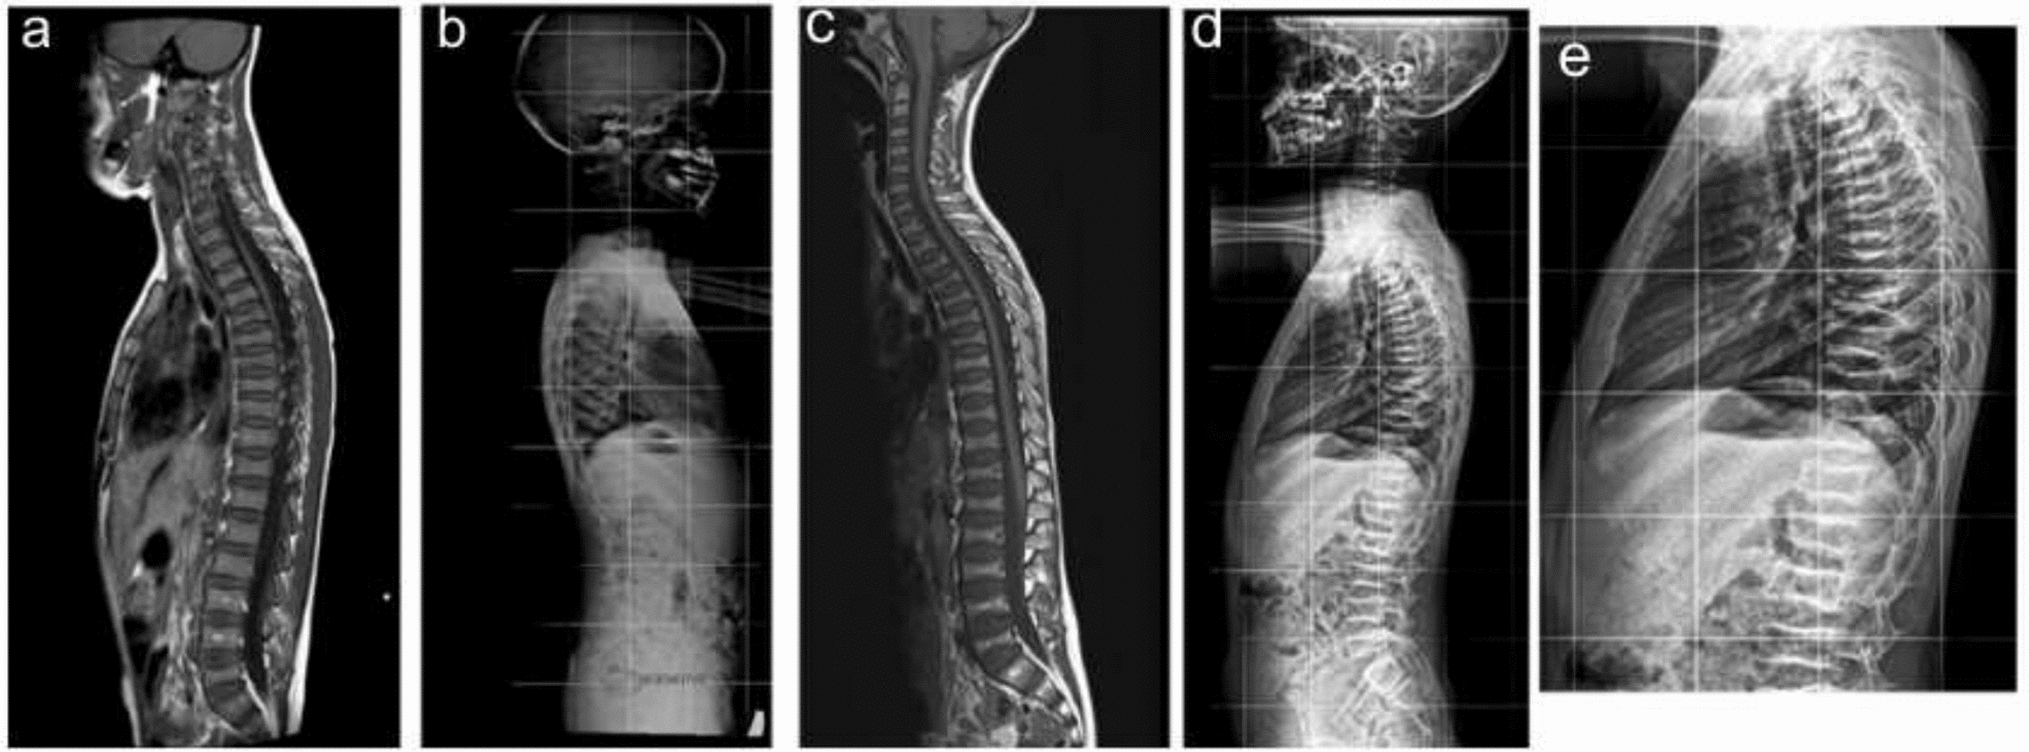

Base of Skull & Spinal Canal Narrowing in an Adolescent with Autosomal Recessive Hypophosphatemic Rickets Type 2